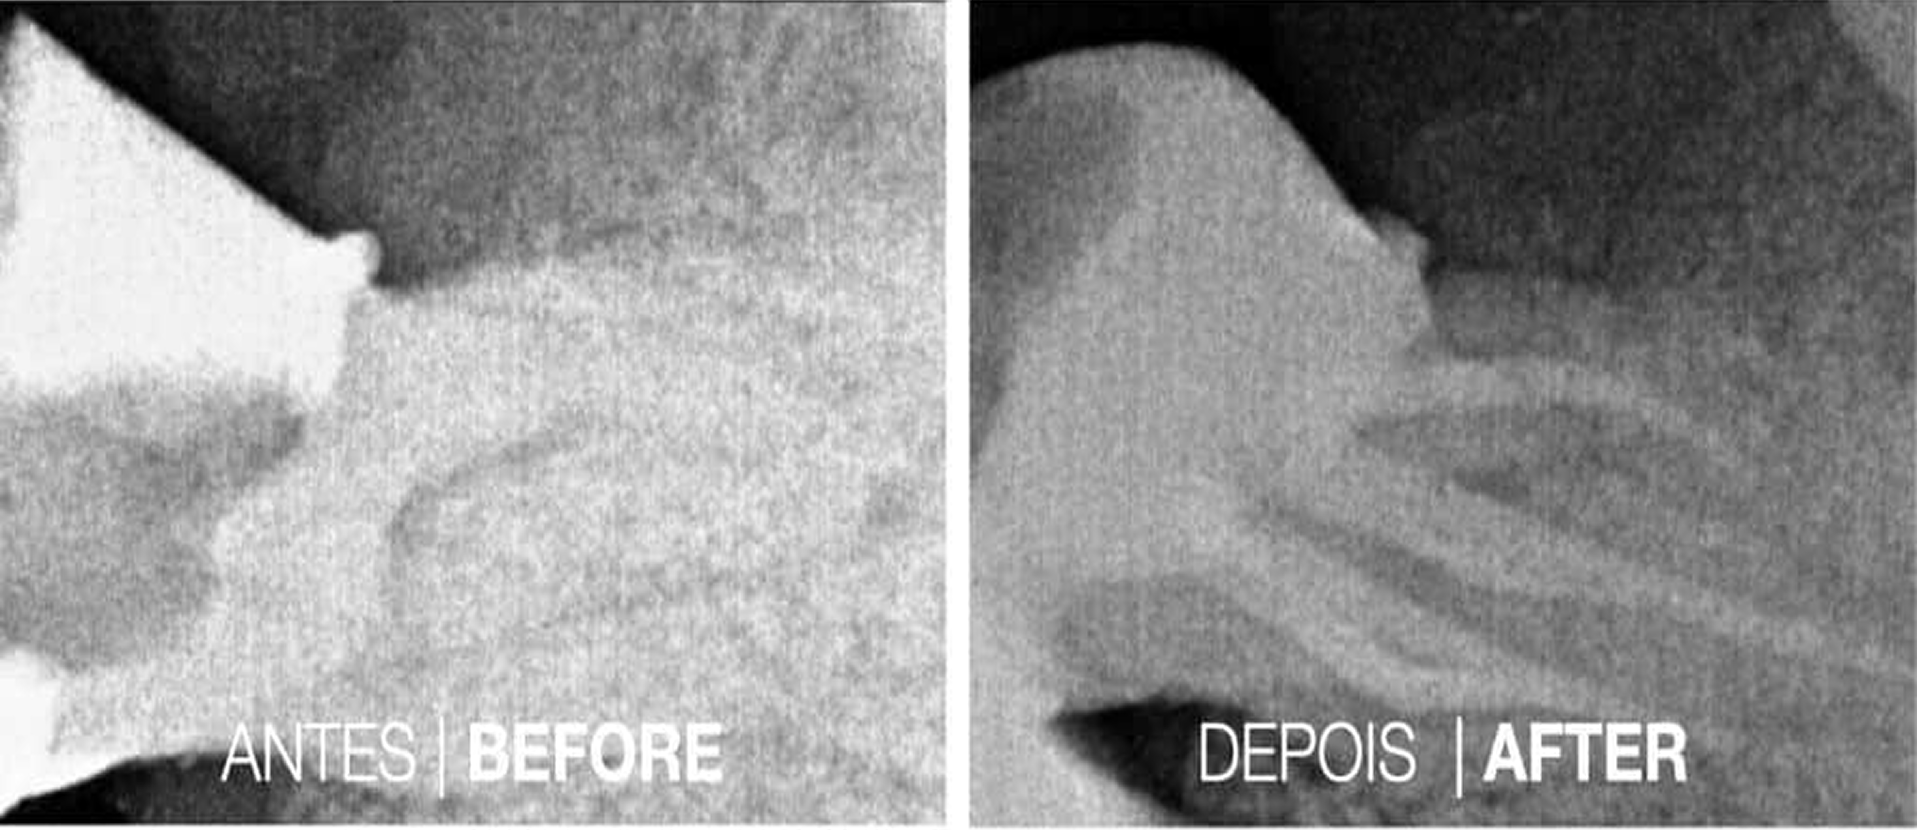

Casos Clínicos

Casos Cínicos concretos que revelam a eficácia do tratamento.